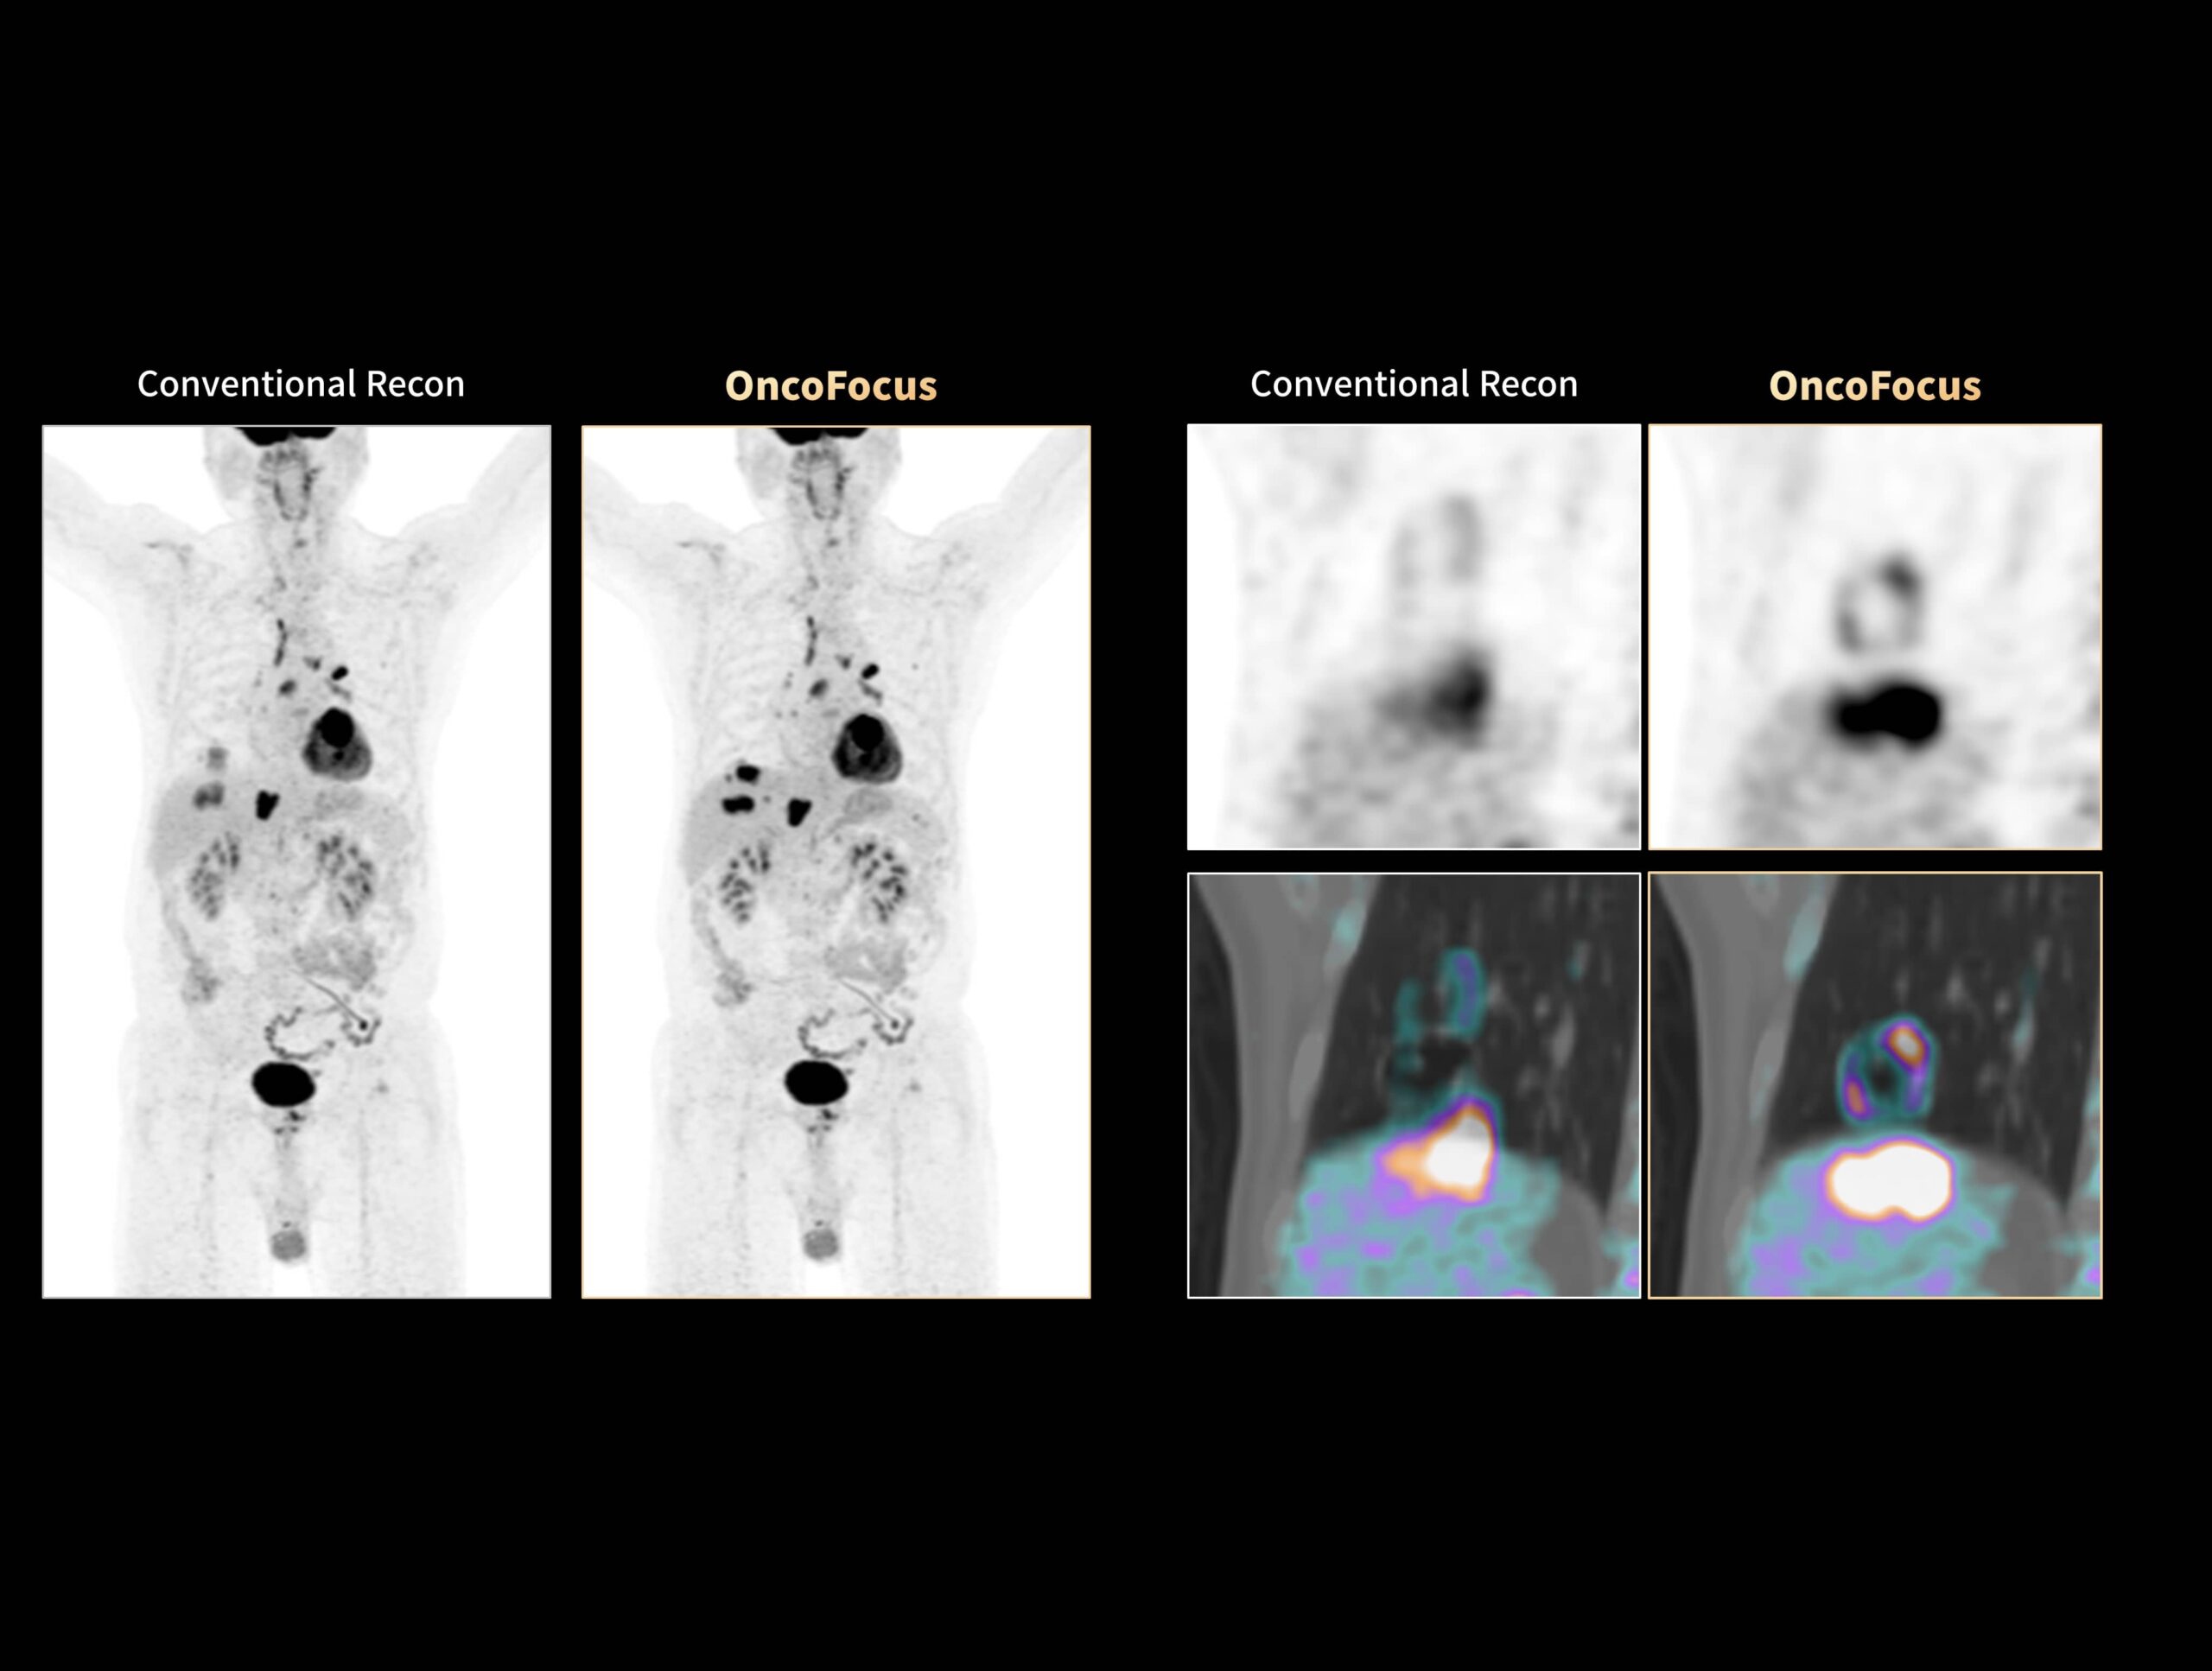

OncoFocus evidențiază clar leziunile hepatice și gastrice

OncoFocus evidențiază clar nodulii pulmonari subcentimetrici

Cancerul pulmonar cu metastaze hepatice greu vizibile poate fi detectat cu OncoFocus

Leziunile nediagnosticate ale osteosarcomului cu metastaze hepatice și pulmonare pot fi vizualizate cu OncoFocus